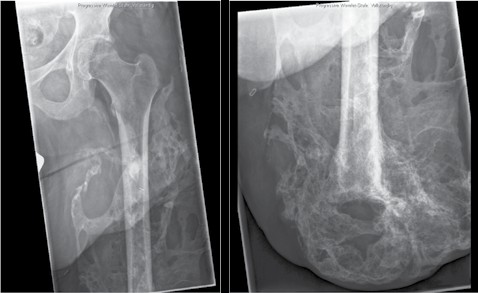

Knochenkanten und Exostosen, die zu nicht prothesenfähigen Stümpfen führen, können einfach reseziert und geglättet werden, teilweise in Kombination mit weichteilverbessernden Maßnahmen. Heterotope Ossifikationen stellen ein größeres Problem dar (Abb. 4). Sie treten bei ca. 23 % der zivilen Patienten nach Amputationen auf, unabhängig von der Ätiologie 9, und bei ca. 63 % der kriegsbedingten Amputationen 10. Bei den kriegsbedingten Amputationen stellten Explosionsverletzungen und Amputationen direkt im Bereich der Verletzung einen Risikofaktor für die Entstehung heterotoper Ossifikationen dar 11. Ferner sind heterotope Ossifikationen häufig mit Rückenmarks- und Hirnverletzungen assoziiert. Die Revisionsoperationen sind häufig nicht nur groß und aufwendig, sondern auch mit hohen Komplikationsraten behaftet. Als Komplikationen treten beispielsweise Blutungen sowie Wundheilungsstörungen auf. Erfreulicherweise können die meisten Komplikationen gut beherrscht werden, und die Patienten erlangen weitestgehende Schmerzfreiheit und prothesenfähige Stümpfe. Patienten, die trotz der Revisionsoperation keine prothesenfähigen Stümpfe erlangen, bedingt z. B. durch Reossifikationen, können auch der Osseointegration zugeführt werden. Auf die Osseointegration wird in diesem Beitrag ebenfalls nicht weiter eingegangen, da sie bereits in einem vorausgegangenen Beitrag ausführlich behandelt wurde 12.